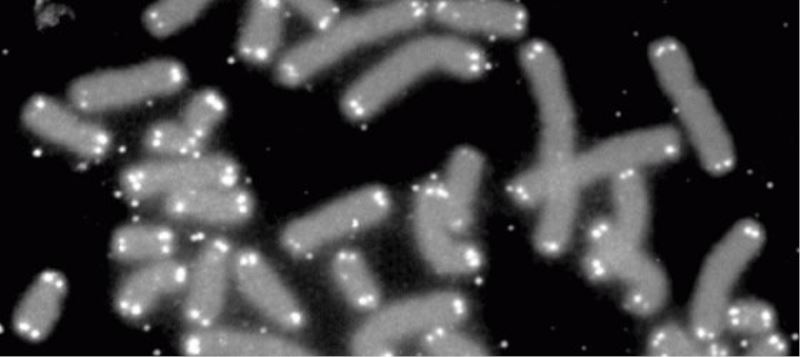

Yeni bir makale, yasla beraber normalde kisalan ‘telomer’ isimli kromozom uçlarinin, diyet, alistirma, ve stressiz ortam sayesinde insanlarda tekrar uzayabilecegine isaret etti.

Kromozomlar, proteine sarilmis uzun DNA molekülleridir. Insanda her bir vücut hücresinde 46 adet bulunur. Kromozomlarin en uç bölgelerine telomer denir. Hücre bölünmesi sirasinda DNA`yi kopyalayan enzimler, bu uç bölgeleri kopyalayamaz. Dolayisiyla vücut hücrelerinin her bölünmesinde telomer bölgeleri bir miktar kisalir. Telomerler tamamen tükendiginde, hücre bölünmeyi durdurur, çalismaz hale gelir, bazen de intihar eder.

Akyuvarlardaki telomerlerin uzunlugunun, çocukluktan itibaren yasla beraber azalma egiliminde oldugu daha önce bulunmustu. Dokularin yasla beraber zayiflamasi ve is göremez hale gelmesinin bir sebebinin de telomer kisalmasi oldugunu düsünülüyordu.